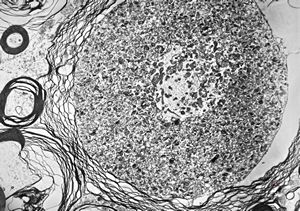

M,21y. | germinoma